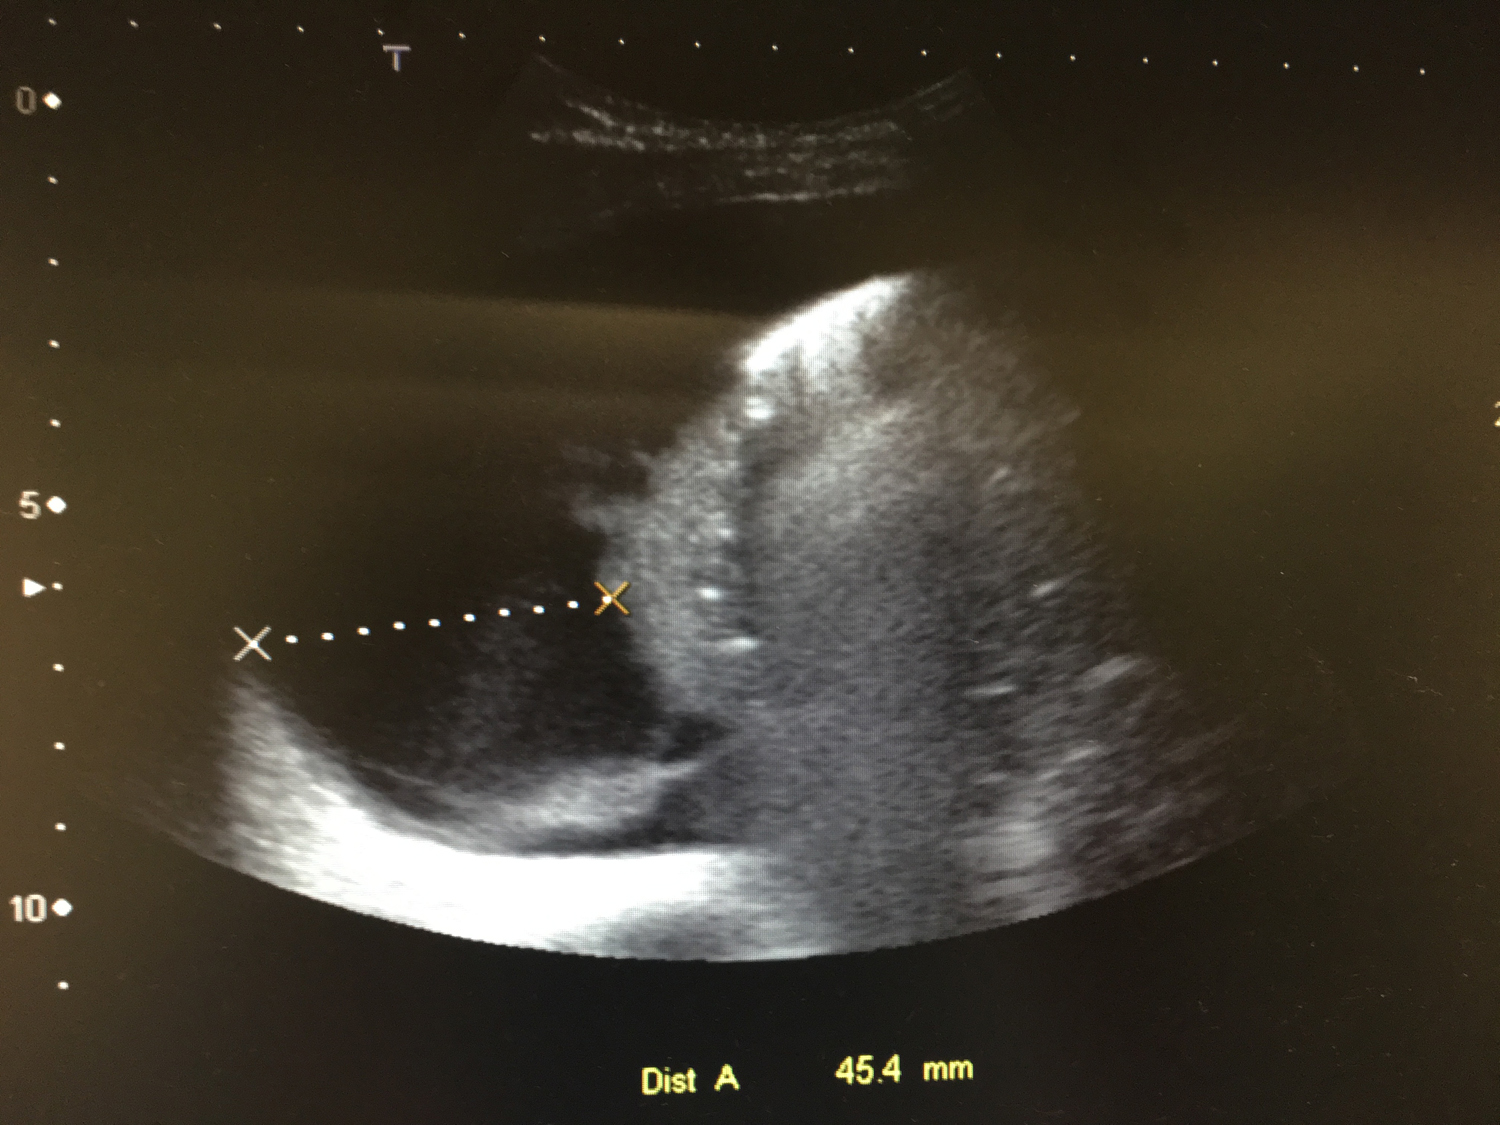

Se decide iniciar cefotaxima a 150 mg/kg/día. A las 12 horas, el paciente persiste febril, pero inicia un aumento de dificultad respiratoria con regular estado general y SatO2 al 96%, con gafas nasales a 1 litro. Se realiza radiografía de control en la que se observa empeoramiento, con aumento de la condensación y ecografía torácica con derrame pleural > 40 mm.